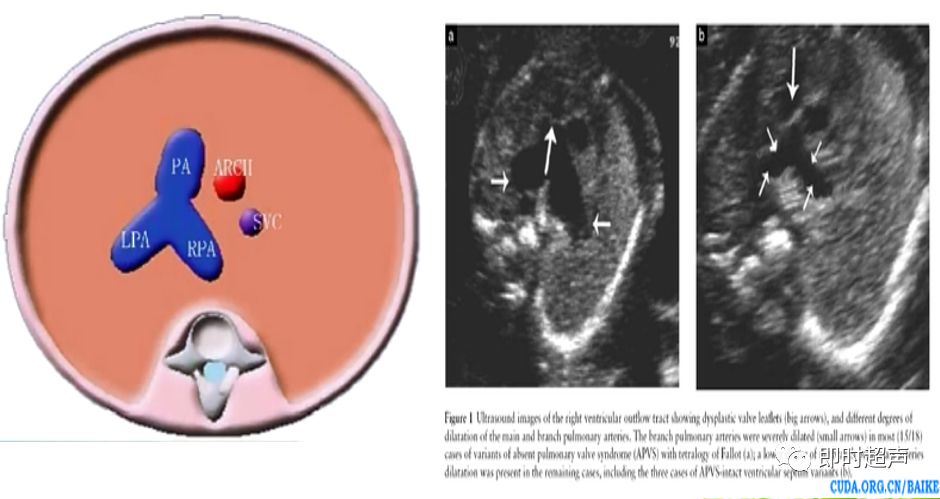

肺动脉增粗、主动脉正常

肺动脉瓣缺如症

- 主要包括:法洛四联症、肺动脉瓣缺如综合症、伴室间隔缺损的肺动脉瓣闭锁、左(右)室双出口、大动脉转、永存动脉干